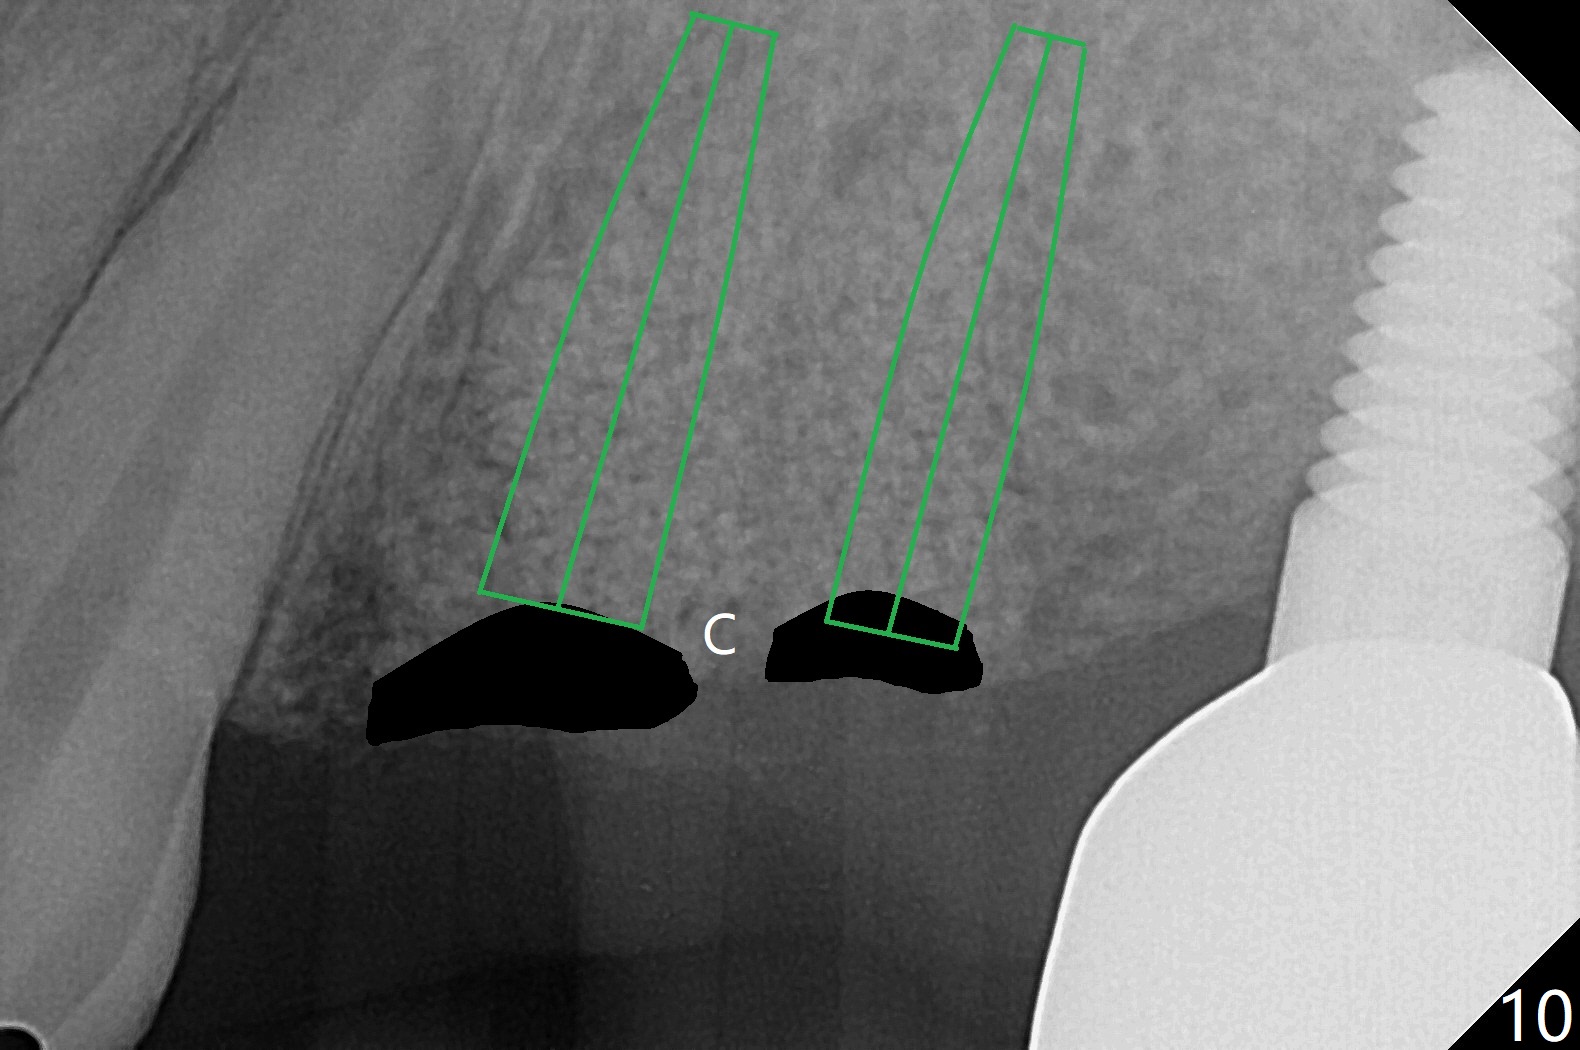

42岁女,12号牙断裂(图一),在拔除中不幸损伤13号牙,一起拔除,用GEM21S与异体骨和人工骨进行位点保存,术后骨粉一直脱落,病人觉得伤口有臭味。术后16天根尖片显示骨粉仍在牙槽窝(图二),伤口尚未愈合(图三),骨粉密度不高(图四,五)。讨论后,决定去除余留骨粉,重新刮拔牙槽窝,反复冲洗,最好放置粘性骨粉(图六),覆盖PRF和不可吸收膜,使用PTFE缝线,树脂敷料。术后三周膜和骨粉仍在原位(图七,八)。为了恢复龈乳头,术后四,五个月,利用导板去除两个牙位牙槽嵴骨质(图九),把植体植入牙槽嵴深部,之间便形成突起的牙槽嵴(图十:C)以及龈乳头。植牙整合后,利用临时牙冠,反复调整,挤压形成比较正常龈乳头。